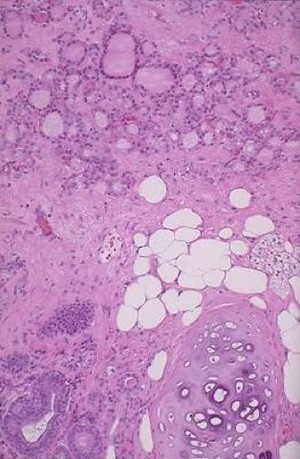

Below: teratoma with adipose and thyroid papilary tissue

Dermoid cyst- mature teratoma

Ovarian germ cell teratoma: see somatic differentiation within germ cell. This is a mature teratoma (recovered from ovaries- therefore germ cells) and is much more likely to be benign. An immature teratoma is found in other tissues, is composed of embryonic tissue and is malignant (totipotent cells with 3 germ layers)

Though benign, these tumors grow other cell types within them that can transform into malignancy (ex. skin can lead to squamous cell carcinoma, or thyroid tissue can lead to papillary thyroid carcinoma)